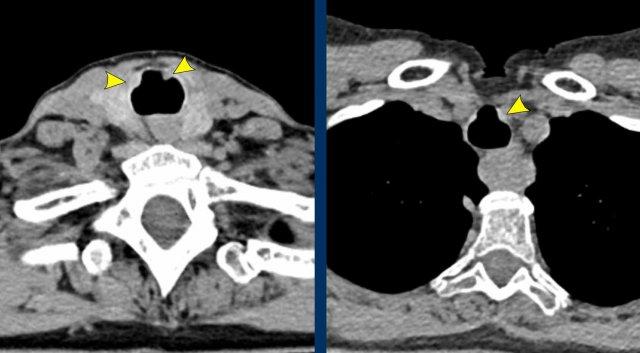

Hình ảnh

Viêm đa sụn tái phát ở bệnh nhân nữ 55 tuổi, cho thấy dày thành đường thở trung tâm do viêm với hình ảnh đặc trưng hình móng ngựa (đầu mũi tên). Không có dày thành sau (mũi tên vàng).

Tổn thương đường thở trung tâm trong GPA cho thấy dày thành khí quản theo chu vi ở mức carina ở bệnh nhân nam 43 tuổi. Có xẹp phổi trái do tổn thương mạn tính của phế quản gốc trái gây hẹp lòng.